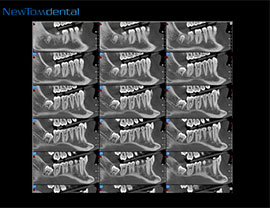

深圳愛康健口腔醫院使用的意大利NewTom VGi新型立式口腔錐形束CT、韓國怡友口腔三維全影像CT機可以為(wei) 醫生和**提供了更精準、更直觀的三維顱骨解剖資料,而且超強的影像清晰質量,有利於(yu) 醫生更準確地把握顧客的口腔狀況,從(cong) 而更準確地診斷牙齒病情。